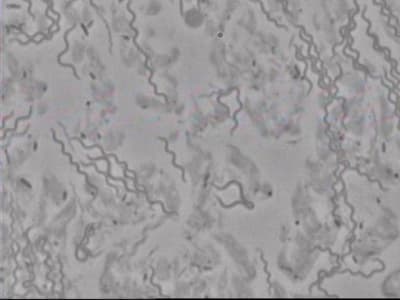

les spirochètes.

la seconde image à mon avis grand filament actinomyces + bacilles .

Je me rappelle du trichomonas, on dirait un blob avec une tête chercheuse, peu ragoutant.

Mais j'adore aussi les spirochètes, avec leur mouvement, on dirait une danse hystérique.